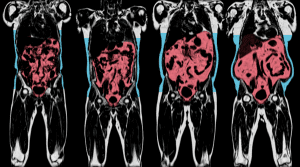

A világ legnagyobb egészségügyi képalkotó – röntgen, MRI és CT – programja indult

A világ legnagyobb egészségügyi vizuális adatbankjaa Medical Research Council, a Wellcome Trust és a Brit Szív Alapítvány támogatásával Nagy-Britanniában annak érdekében, hogy az emberi belső szervekről készült felvételek legnagyobb gyűjteményét készítsék el.

A 16,8 milliárd forint értékű projekt rengeteg betegség – demencia, ízületi gyulladás, rák, szívroham és agyérkatasztrófa – kutatásának módját változtatja meg gyökeresen az Oxfordi Egyetem honlapja szerint. A programban a UK Biobank adatbázisában szereplők közül 100 ezer résztvevő agyáról, szívéről, csontjairól, nyaki verőereiről és hasi zsírpárnáiról készítenek felvételeket. Utóbbiakról nem olyan régen derült ki, hogy nagyon is befolyásolják a súlyos betegségek jövőbeni kockázatát.